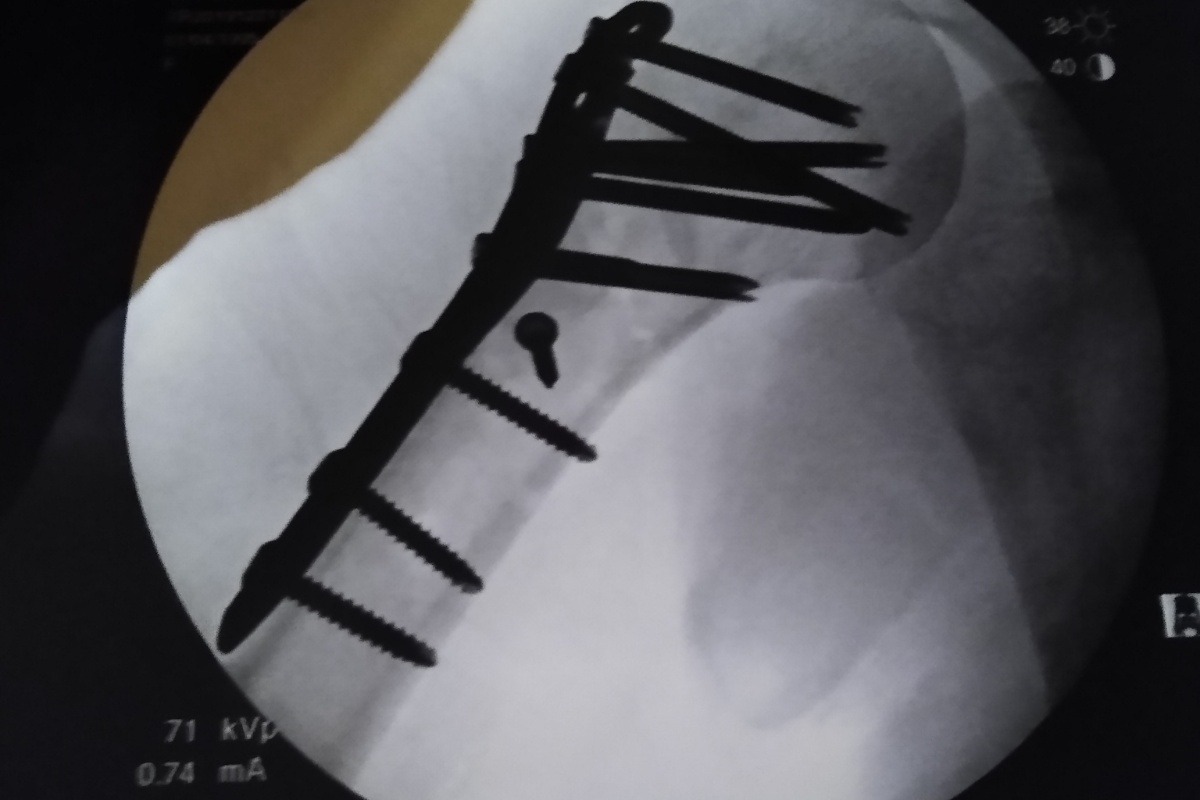

Valerie does not know we are doing this. In December, Valerie broke her humerous in a snow boarding accident. She had 10 screws and a plate to hold it all back together. It got infected, she had to have three additional surgeries. It has now been over 6 months of medical treatments, surgeries, suffering and bills. If you can help, we will appreciate it.